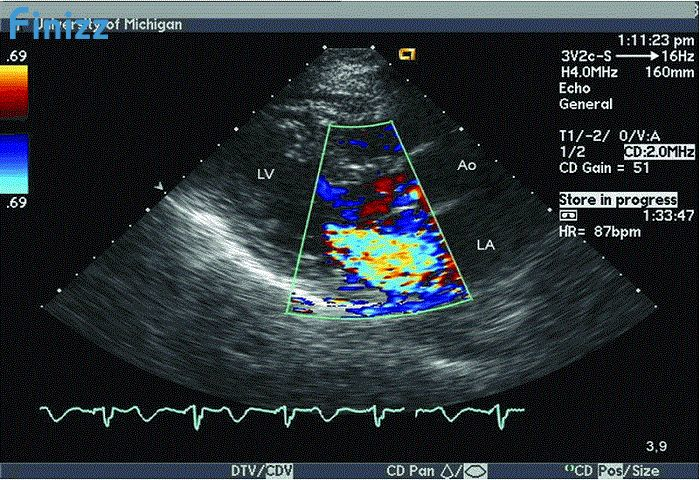

Siêu âm Doppler thai 32 tuần là 1 trong những kiểu siêu âm được sử dụng trong việc thăm khám và đánh giá sức khỏe của bé trong bụng mẹ.